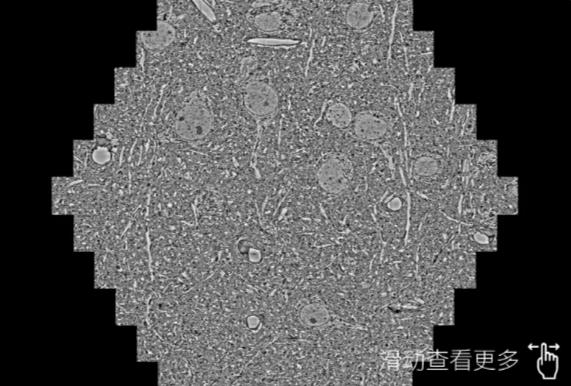

鼠脑切片。左图使用鞍山蔡司鞍山扫描电镜MultiSEM706对165μmx143pm面积区域成像,耗时仅需1.5秒。右图为鼠脑切片中30μm区域放大效果。样品由芝加哥大学B.Kasthuri提供。

使用蔡司高速鞍山扫描电镜MultiSEM对1mm²人脑皮层组织进行高分辨成像,并对其中的各种细胞结构进行三维重构分析。左图展示了2x3mm²组织平面中锥体神经元的三维重构效果。右图显示了局部体积神经元三维重构。图像由哈佛大学chtman实验室提供,渲染图由D. Berger 制作。